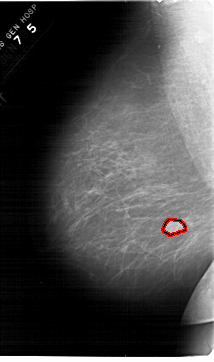

FILE: A_1567_1.LEFT_MLO.OVERLAY TOTAL_ABNORMALITIES 1 ABNORMALITY 1 LESION_TYPE MASS SHAPE LOBULATED MARGINS OBSCURED ASSESSMENT 4 SUBTLETY 4 PATHOLOGY BENIGN TOTAL_OUTLINES 1 BOUNDARY |

FILE: A_1567_1.LEFT_CC.OVERLAY TOTAL_ABNORMALITIES 1 ABNORMALITY 1 LESION_TYPE MASS SHAPE LOBULATED MARGINS OBSCURED ASSESSMENT 4 SUBTLETY 4 PATHOLOGY BENIGN TOTAL_OUTLINES 1 BOUNDARY |